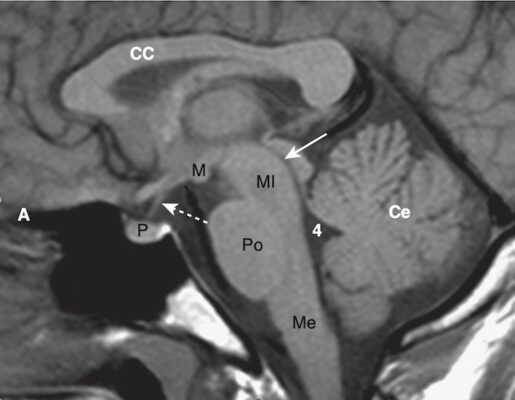

- Ở hố sau (posterior fossa), não thất 4 xuất hiện như một cấu trúc hình chữ U ngược. Tương tự như tất cả các cấu trúc chứa dịch não tủy (CSF, cerebrospinal fluid), nó thường có màu đen trên CT. Phía sau não thất thứ 4 là các bán cầu tiểu não, và phía trước là cầu não và hành tủy. Lều tiểu não (tentorium cerebelli) ngăn cách các thành phần dưới lều của hố sau (hành tủy, cầu não, tiểu não và não thất 4) với khoang trên lều. (Hình 1A)

- Bể chứa gian cuống (interpeduncular cistern) nằm trong não giữa và ngăn cách các cặp cuống não, các cuống này nổi lên từ bề mặt trên của cầu não. Bể chứa trên tuyến yên (suprasellar cistern) nằm trước bể chứa gian cuống và thường có hình dạng giống như hình sao năm hoặc sáu cánh. (Hình 1B)

- Thể chai (corpus callosum) nối bán cầu đại não phải và trái và tạo thành mái của não thất bên. Đầu trước được gọi là genu (gối ), và đầu sau được gọi là splenium (nghĩa là như cuộn băng, dịch là lồi?).

- Sừng (trán) trước của não thất bên ôm lấy đầu của nhân đuôi (Hình 1D, E). Hai sừng trước được ngăn cách bởi vách trong suốt (septum pellucidum) ở đường giữa. Sừng thái dương, bình thường rất nhỏ, ở thấp hơn và nằm trong thùy thái dương. Sừng sau của não thất bên (sừng chẩm) nằm trong thùy chẩm. (Hình 1F) Phần cao nhất của hệ thống não thất là các thân của não thất bên.

Hình 1. Chụp cắt lớp vi tính đầu bình thường không cản quang.